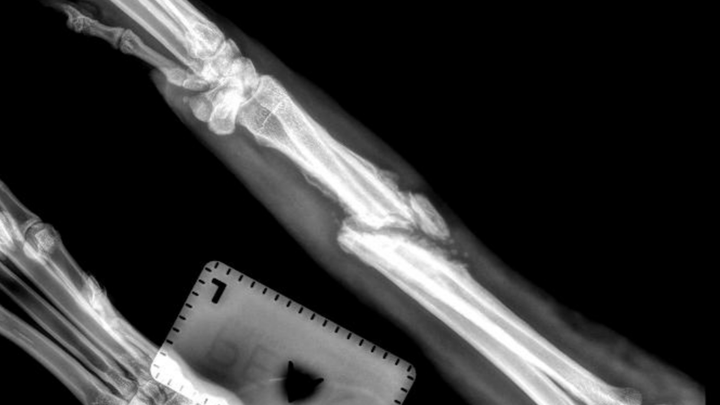

I found Keno (formerly Louise) days after losing my last rescue, Maci, to terminal lung cancer. It was quick, and I wasn't looking for another dog, but then I saw an urgent post asking if anyone could help. Keno was on the "Kill list," and was days away from being euthanized. On top of that, he had a broken leg; the extent of the break was unknown at the time as the shelter that had him would not disclose the severity. After seeing the X-rays, it is tragic he sat there for 2 months in this condition.

Unfortunately, at this point, our vet is recommending amputation due to the severity of the break and because it went without proper treatment for so long. Surgery is still not out of the question but will be equally as expensive.